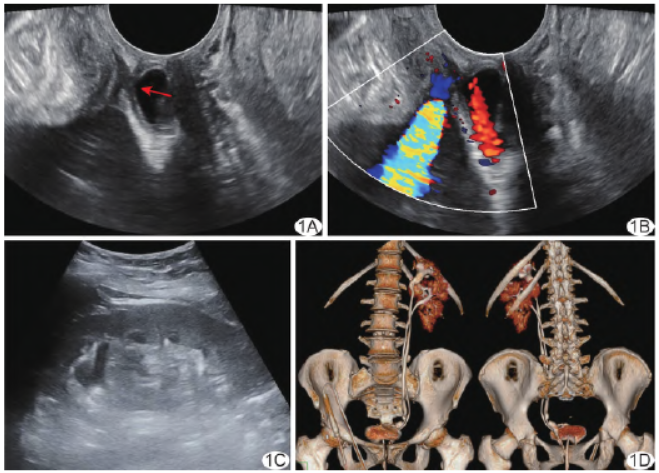

实验室检查无特殊。盆底超声:子宫外左前方紧贴膀胱处2.94 cm ×1.22cm×1.79cm 囊性占位,似经尿道中段后壁回声中断处与尿道相通(图1A),其形态、大小可见改变;CDFI示其内液体间歇性向尿道流动,到达尿道后大量经尿道上段反流回膀胱、少量流向尿道外口(图1B)。

经腹超声:左肾内见2组不相连的肾窦回声,上组集合系统分离内径约0.93cm(图1C);左侧输尿管中下段最宽处内径约0.71cm,向下与膀胱后方的囊性占位相连;意见:疑似输尿管异位开口于尿道、左侧重复肾伴左侧输尿管扩张。

泌尿系统增强CT:左肾见2个肾盂及输尿管,上份肾盂及输尿管稍扩张,末端位于尿道,下份输尿管末端位于膀胱内(图1D);提示:左侧重复肾、上份输尿管开口异位。行全麻下腹腔镜左侧异位输尿管膀胱再植+输尿管成形术,术中见左侧正常及异位输尿管,其上份开口于尿道。最终诊断:左侧重复肾合并上份输尿管开口异位。

图1 左肾重复肾合并上份输尿管异位开口 A.盆底声像图(箭示囊性占位与尿道相通处);B.盆底CDFI;C.腹部声像图;D.泌尿系统增强CT正面观(左)及背面观(右)容积漫游重建图